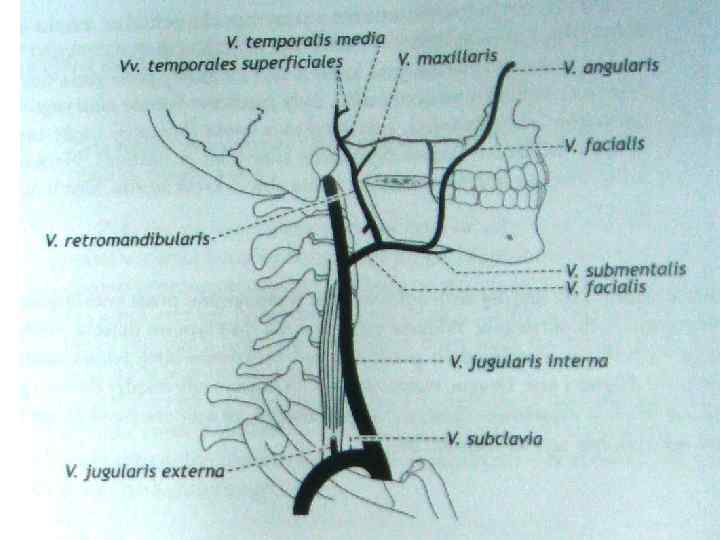

Анатомия внутренней яремной вены: КТ изображения